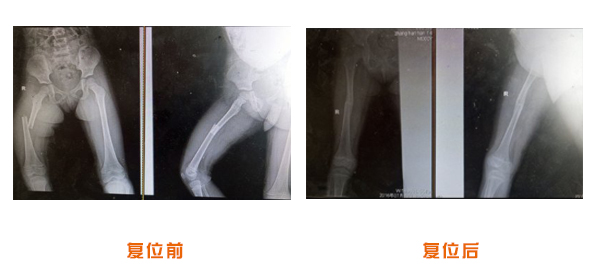

肥城市安駕莊梁氏骨科醫(yī)院是一所以梁氏手法正骨配合膏藥為特色的現(xiàn)代化??漆t(yī)院。

梁氏骨科術(shù)始創(chuàng)于清雍正年間,歷經(jīng)八代,至今已有三百年歷史。據(jù)1929年泰安縣志載“梁瑞圖先生,字增生,號蓮峰,安駕莊人,精岐黃并發(fā)明接骨,凡跌打車凡跌打車軋皮不破而碎骨者......【詳細(xì)】 |